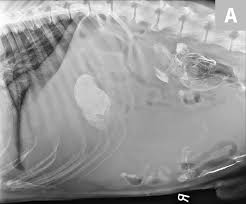

Both spleen tumors cause the same symptoms: Your options for splenic hemagiosarcoma. Sometimes this cancer may cause weakness, especially in the hind legs, and decreased energy that lasts for a day or two, then goes away only to reappear weeks or months later. The blood from the spleen leaks into the abdomen, causing anemia and shock from loss of blood. Chronic weakness, lack of appetite, weight loss), abdominal swelling, collapse and acute death if the tumor ruptures and bleeds internally.

Symptoms of canine spleen cancer dogs with hemangiosarcoma in the spleen may not show any symptoms at the early stage. It's important to rush your dog to a veterinarian if any of these signs occur. While it is less frequent compared to liver cancer, for example, spleen cancer can be seen in a number of cases. Most dogs presenting with this cancer are brought to their veterinarian by their owners on an emergent basis due to a range of nonspecific clinical signs such as: Sometimes, it isn't found until one of the tumors ruptures and causes internal bleeding. Symptoms are generally related to the organs involved; How common is cancer in dogs, and what are some of the common. Only after an autopsy is the cancerous tumor on the spleen discovered. What are the symptoms of spleen tumors in cats and dogs? When to euthanize a dog with hemangiosarcoma Unfortunately, one of the most common initial signs of hemangiosarcoma involves sudden collapse due to massive internal bleeding, usually from a ruptured spleen. Chronic weakness, lack of appetite, weight loss), abdominal swelling, collapse and acute death if the tumor ruptures and bleeds internally. What are the symptoms of spleen cancer in dogs?

Studies find that 1 out of 4 dogs with cancer of the spleen also have tumors on their heart. When to euthanize a dog with hemangiosarcoma Due to its insidious nature, a ruptured spleen caused by a malignant cancer in dogs, is often nicknamed as the silent killer. veterinarian dr. Tumor is found only in the spleen. The spleen is a very important organ in the body and it plays important roles in rbc regulation and the immune system of the pet. What are the symptoms of spleen tumors in cats and dogs? Since dogs usually show only mild warning signs, cases of hemangiosarcoma may not be detected until the cancer has reached an advanced stage. — lump in the abdominal area Often, a tumor will rupture causing the spleen to bleed and resulting in an internal hemorrhage. If a dog has splenic hemangiosarcoma, it means the cancerous blood vessels are located in the tissue of your dog's spleen. Some of the symptoms that pet parents can be on the lookout for: It is a cancer made up of the cells that line blood vessels, and therefore can be found in any part of the body. Symptoms of dog spleen cancer are nonspecific;